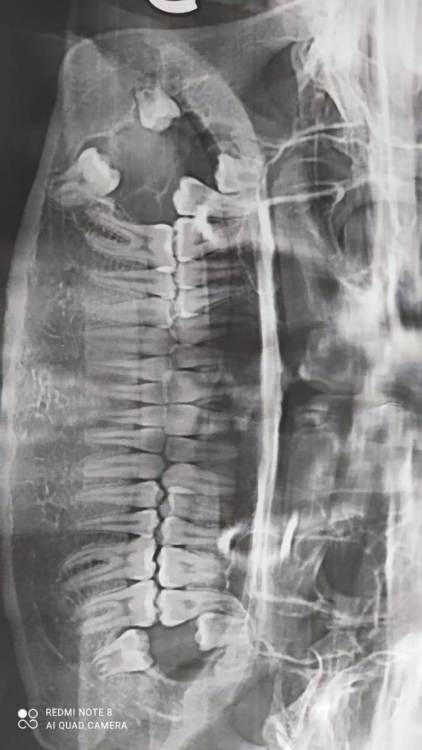

В 2021 году у дочери выявлено новообразование в нижней челюсти справа (киста под  вопросом). Обратились  в местный хирургический   центр,  мнения специалистов разошлись, один  рекомендовал удаление образования, другой озвучил, что лучше не трогать, есть риск затронуть лицевой нерв.

В этом году появились боли, сделали повторно КТ, диагностировали увеличение образования + разрушение кости, является помехой роста рядом стоящих зубов. Рекомендовано удаление, но гарантию положительного исхода местные специалисты не дают.

Снимки прилагаю. Порекомендуйте, пожалуйста, специалиста, к  которому можно обратиться для лечения/удаления образования.

2022.jpeg